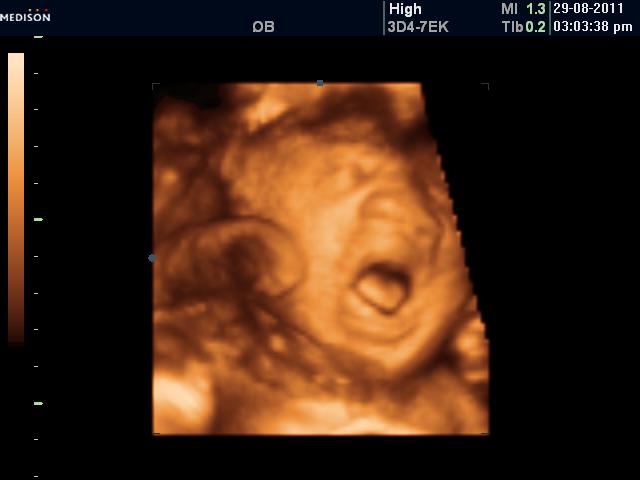

4D scan of Jah…:D

I know it looks abit scary…

But really fun to see his expression and imagine what he might look like..